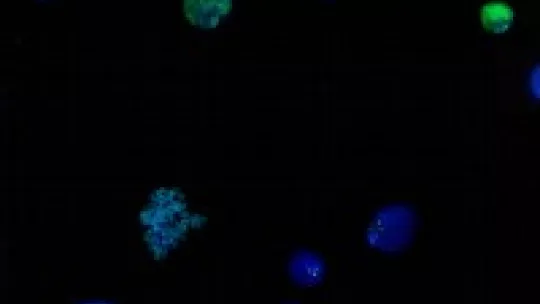

Epigenetics emerged on the scene in the 1990s. Researchers discovered that chromatin, the complex formed by DNA and histones, -proteins that bind strongly to DNA, thereby packaging it in chromosomes-, regulate gene expression. This additional layer of regulatory instructions, which are not held in DNA, comprise the epigenetic code.

Epigenetic differences explain, for example, why two cloned organisms are not the same or why twins develop illnesses of distinct genetic origin. Epigenetic studies promise not only to have a direct impact on health and our understanding of the relations between the environment and genetics but also to provide an explanation of basic aspects of cell biology. The co-organiser of the conference, Ferran Azorín, head of the “Chromatin Structure and Function” group at IRB Barcelona, comments that “deciphering and understanding the epigenome will shed light on fundamental processes in cell physiology. This knowledge will improve our understanding of the development of tumours and other diseases, and may lead to the design of new treatments for these conditions”. A new family of epigenetic drugs, designed to reverse the changes in the epigenome that occur during the development of several kinds of cancer, is currently available. Several of these pharmacological agents are now being used to treat some types of leukaemia and breast cancer.